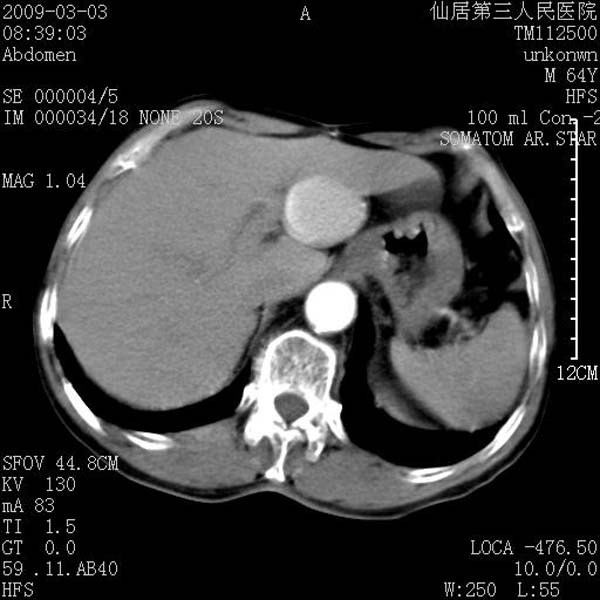

标题: CT18469:男性,64y,体检B超示肝脏低回声肿块,有胃溃疡手术 [打印本页]

标题: CT18469:男性,64y,体检B超示肝脏低回声肿块,有胃溃疡手术

患者,男性,64y,体检b超示肝脏低回声肿块,有胃溃疡手术史。

考虑----胃肠道间质瘤可能性大

从平扫及增强的特点来看,支持肝脏腺瘤并出血。

考虑胃间质瘤可能性大。

胃肠道间质瘤!

ct值呢?感觉没强化,象囊性。

考虑肝静脉韧带裂区良性占位性病变(囊肿?)。

考虑肝囊肿并出血可能性大.

考虑高密度囊肿可能性大